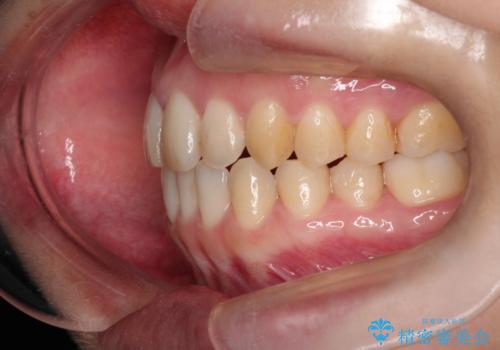

本症例は、見た目、嚙み合わせ及び、治療期間や施術内容にご満足いただきました。